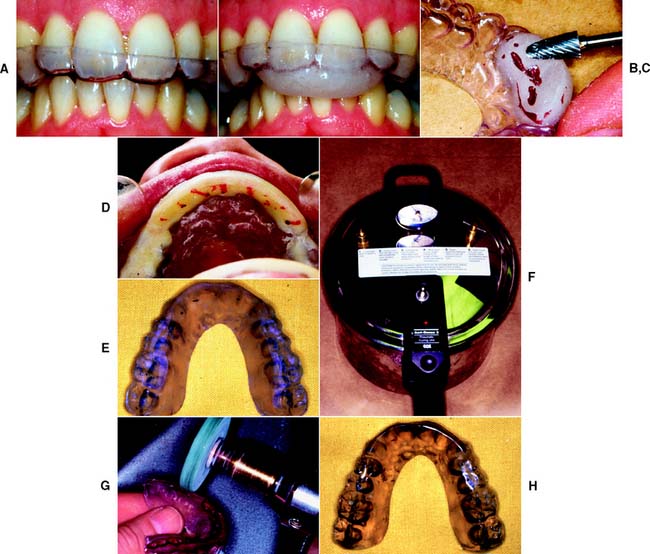

Oral habits consisting of involuntary rhythmic or spasmodic nonfunctional gnashing, grinding, or clenching of teeth, in other than chewing movements of the mandible, that may lead to occlusal trauma is known as bruxism (Fig. 4-18). This activity may be diurnal, nocturnal, or both. Although bruxism is initiated on a subconscious level, nocturnal bruxism is potentially more harmful because the patient is not aware of it while sleeping. Therefore, it can be difficult to detect, but it should be suspected in any patient exhibiting abnormal tooth wear or pain. The prevalence of bruxism is about 10% and is less common with age.18 The etiology of bruxism is often unclear. Some theories relate bruxism to malocclusion, neuromuscular disturbances, responses to emotional distress, or a combination of these factors.19 A study on cohort twins has demonstrated substantial genetic effects20; the condition has been related to sleep disturbance21; and the symptoms of bruxism are three times more common in smokers.22 Altered mastication has been observed in subjects who brux23,24 and may result from an attempt to avoid premature occlusal contacts (occlusal interferences). There may also be a neuromuscular attempt to “rub out” an interfering cusp. The fulcrum effect of rubbing on posterior interferences creates a protrusive or laterotrusive movement that can cause overloading of the anterior teeth, with resultant excessive anterior wear. It is common for wear on anterior teeth to progress from initial faceting on the canines to the central and lateral incisors. Once vertical overlap diminishes as the result of wear, posterior wear facets are commonly observed. However, the chewing patterns of normal subjects can be quite varied, and the relationship, if any, between altered mastication and occlusal dysfunction is not clear.25

Fig. 4-18 Extensive abrasion (tooth wear) resulting from parafunctional grinding.

(Courtesy of Dr. M. Padilla.)